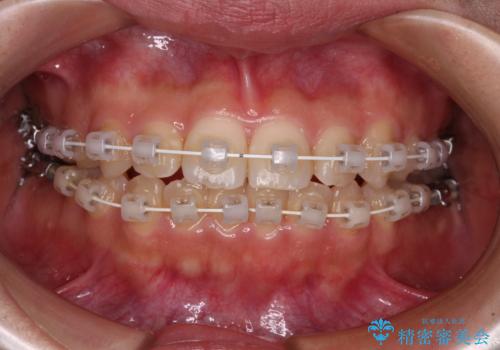

- 矯正装置

- 審美装置

当初予定通り、1年で治療を終えることができました。

後戻り防止はマウスピースで行うため、急に自己管理が必要となるため、移動の最後をマウスピース矯正で行うことで、マウスピース非装着による後戻りリスクを回避する工夫をしています。